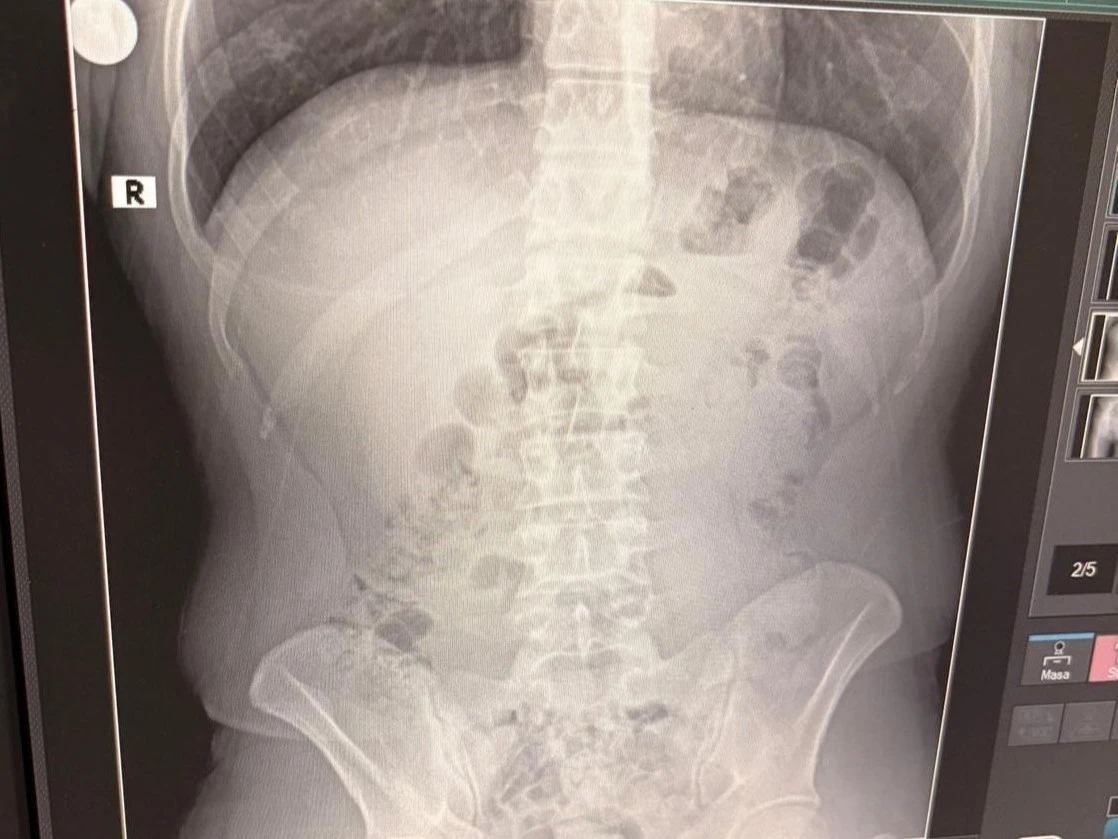

Adreste yapılan arama sırasında ekipler, şüphelilerden birinin üstünde 1 adet kapsül ele geçirdi. Şüphe üzerine tüm şüpheliler hastaneye götürüldü ve yapılan röntgen kontrollerinde 3 kişinin midelerinde kapsül içine gizlenmiş metamfetamin tespit edildi.

Hastanede tedavi altına alınan şüphelilerin vücudundan kapsüller çıkarılırken, adreste ele geçirilenlerle birlikte toplam 1 kilo 516 gram metamfetamin ele geçirildi.